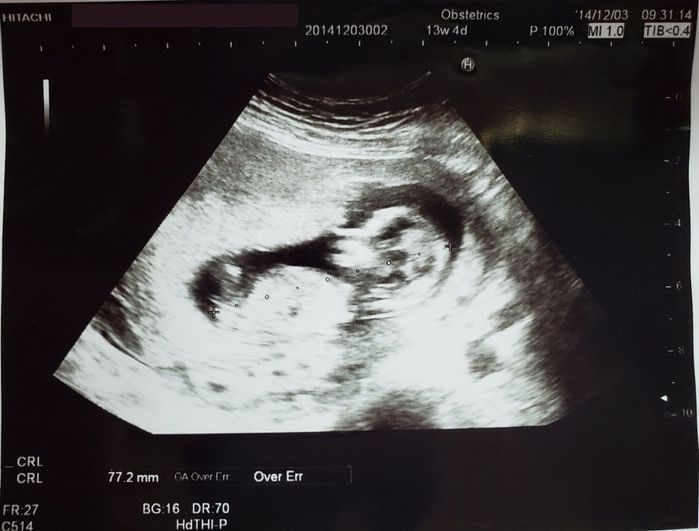

妊娠13週目のエコー写真 - 赤ちゃんが成長している!

前回よりも赤ちゃんが大きくなっており、背骨も確認できました。それでも赤ちゃんが問題なく成長しているか心配はつづき、健診のたびに先生に「大丈夫ですか?」と聞いていました。安定期と呼ばれる16週が待ち遠しかったのを覚えています。このころはまだ「つわり」がつらい時期でしたが、赤ちゃんのために毎日たくさん散歩をしていました。